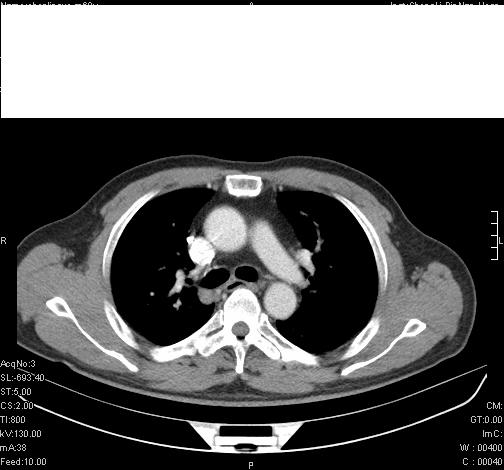

标题: CT6685:右肺阻塞性炎症,增强CT。

前几天,发了患者的平扫片,患者抗炎一周后增强扫描。右中叶病灶吸收明显,但下叶病灶未见明显吸收。右肺门可见结节影,看来凶多吉少

第18幅,好像不能简单用炎症解释,前几天我发平扫时,90%人支持肺癌,现在好像大家更倾向于炎症了,我觉得还是不能排除肺癌。

右肺下叶支气管壁明显增厚,考虑癌症并阻塞性炎症、肺门淋巴结肿大

还是考虑右肺中央型肺癌可能性大

考虑右肺中央型肺癌可能性大

右主支气管狭窄,管壁增厚。考虑右中心性肺ca伴阻塞性肺炎。